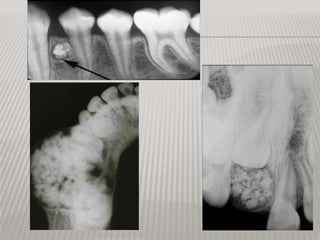

COMPLEX ODONTOMA RADIOGRAPHICLLY

 radiographically "sunburst radiopacities, thin

uniform radiolucent rim

 similar description as osteosarcoma, but assoc

w/ tooth, clear of bony borders

•   large radioopaque

lesion

•   well encapsulated w/

radioiolucent border

COMPLEX ODONTOMA RADIOGRAPHICLLY Common lesions that persist through life  Usually detected in adolescence  most commonly in mandibular molars  not painful, or swelling  radiographically "sunburst radiopacities, thin uniform radiolucent rim  similar description as osteosarcoma, but assoc w/ tooth, clear of bony borders

• 15.

large radioopaque lesion • well encapsulated w/ radioiolucent border